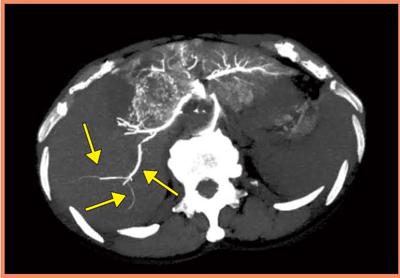

当センターでは,肝臓がんに対する動注リザーバー療法を行っている。本療法では,抗癌剤の薬剤分布が重要な要素となる。このfirst pass effectを確認するため,CTによるフローチェックを行っている。

大腸がんの肝転移症例(図3)では,3D-CTAにおいて背側の結節まで濃染され,薬剤の肝内分布も良好に見えたものが,4D-CTAにおいて背側の結節に向かう血管内で血流が押し戻されている様子が確認できた。リザーバーからの抗癌剤注入は,CT撮影時の造影剤の圧入と異なり,スローインフュージョンとなるが,このような状況下では十分な薬剤分布が得られていないと考えられた。実際に,背側部では治療効果が得られず,ADCTの4D撮影によるフローチェックによって,薬剤効果の判定が可能になると考えられる。

図3 4D-CTによる大腸がん肝転移症例の動注リザ―バー療法での

フローチェック

背側側に向かう血管の血流が押し戻されている様子が描出された(→)。